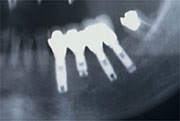

治療風景

下顎右側4本欠損

![]() |

| レントゲン写真 | 治療後 |